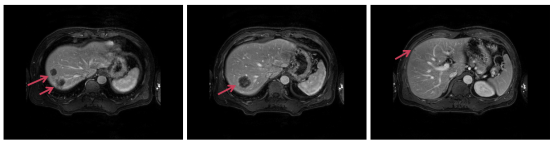

2020.09.25 上腹部MRI影像:肝内多发占位性病变(6个),考虑多发转移瘤。

image.png

图2 初诊时上腹部MRI

2021.04复查影像评估提示:肝右叶膈顶S7 及胆囊窝转移瘤较前减小,仍有活性。

图6 影像评估提示肝右叶膈顶S7 及胆囊窝转移瘤较前减小,仍有活性

2021.08.24上腹部MRI显示肝转移瘤1(胆囊窝)无活性,肝转移瘤2(膈顶)有活性。

图7 影像评估提示肝转移瘤1(胆囊窝)无活性,肝转移瘤2(膈顶)有活性